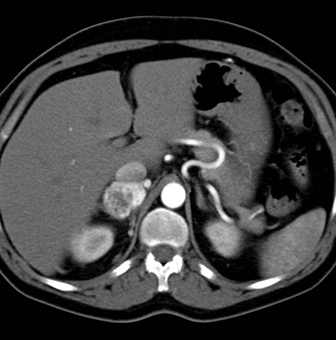

The best diagnosis in this case is?

adrenal lymphangioma

adrenal lymphoma

pheochromocytoma

adrenal carcinoma